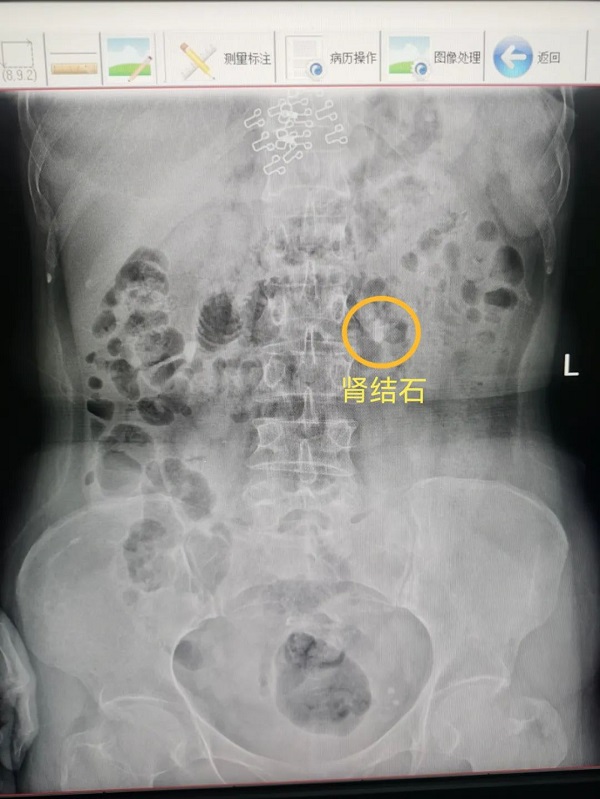

65岁杨大姐和50岁的潘大姐就是这种手术的受益者,她俩均因为腰痛来我院泌尿外科门诊咨询就诊,医生诊断为肾结石,并建议她们做输尿管软镜手术治疗,通过医生的详细介绍,杨大姐和潘大姐对这种没有任何刀口的手术方式表示很惊讶,紧张的心情一下子就放松了。

通过应用负压吸引鞘,主任医师辛明辉、副主任医师刘伟带领泌尿外科团队在麻醉医师的通力合作下,对结石进行了完全清除,手术均顺利完成。经过术后康复,杨大姐和潘大姐在手术后第三天就顺利出院了。